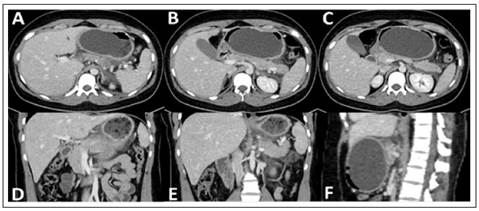

Paciente mujer de 20 años, natural de Lima, de ocupación estudiante, con antecedente de colocación de balón intragástrico (Elipse™ balloon, Allurion Technologies), bajo supervisión radiológica 4 meses atrás debido a sobrepeso (peso inicial 85 Kg, talla 1,73 m, IMC 28 kg/m2); a partir del cual, refiere episodios de dolor abdominal de intensidad leve a moderada, que ocurren durante el reposo en posición decúbito ventral, con resolución espontánea al despertar y cambiar de posición; sin otros antecedentes de importancia. El cuadro clínico actual se inició durante un viaje al extranjero, con un tiempo de enfermedad de 6 días previos a la evaluación en nuestro servicio, caracterizado por dolor abdominal de inicio súbito, de 1 día de evolución, localizado en epigastrio, intensidad 10/10, que apareció durante el sueño, mientras se encontraba recostada sobre la posición decúbito ventral; se asocian náuseas persistentes, ausencia de deposiciones, aunque con presencia de flatos. Al examen físico, regular estado general, con funciones vitales estables, lucía álgida, con piel y mucosas hidratadas, sin ictericia; abdomen plano, blando y depresible, con discreto dolor a la palpación de hipocondrio derecho y epigastrio, resto del examen sin particularidades. La analítica mostró respuesta inflamatoria sistémica con leucocitosis (14 000 / mm3, VN 4000 -10 000 / mm3), proteína C reactiva aumentada (39 mg/dL, VN < 6 mg/dL); así como hiperlipasemia 3 veces superior al valor límite normal (189 U/L, VN 13-60 UL), discreta hiperbilirrubinemia total (1,6 mg/dL, VN 1-1,2 mg/dL), bilirrubina directa discretamente elevada (BD 0,3 mg/dL, VN 0-2 mg/dL), y el resto del perfil hepático sin alteraciones; función renal conservada (creatinina sérica 0,7 mg/dL, úrea 27 mg/dL). La tomografía abdominal computarizada mostró edema pancreático a predominio de la cola, con presencia de líquido peripancreático, en las fascias pararrenales, correderas parietocólicas y fondo de saco de Douglas; hallazgos sugestivos de pancreatitis aguda (Figura 1).

Figura 1 Tomografía computarizada en cortes axial, coronal y sagital. A, B y C: Corte axial, muestra páncreas de aspecto heterogéneo, aumento de volumen a nivel de cola pancreática, líquido peripancreático y ascitis laminar perihepática. D y E: Corte coronal, cuerpopancreático de aspecto heterogéneo con aumento de volumen y edema peripancreático. F: Corte sagital, que muestra balón intragástrico a nivel del antro que comprime cuerpo pancreático ante estructuras subyacentes (tronco celiaco, aorta y cuerpos vertebrales).

El diagnóstico de pancreatitis se realiza con la presencia de al menos 2 de los siguientes 3 criterios: dolor abdominal en epigastrio, elevación de 2 a 3 veces el valor normal de las enzimas pancreáticas y los hallazgos imagenológicos típicos 9. Mayoritariamente su etiología se relaciona a patología de la vía biliar y al uso de alcohol, siendo el resto de las causas menos frecuentes. Por lo tanto, requiere de un abordaje diagnóstico apropiado 10. En los pacientes portadores de balón intragástrico, la compresión mecánica sobre el cuerpo y cola de páncreas se postuló como la principal condición precipitante de pancreatitis, que puede ser evaluada de mejor manera en estudios de imagen transversal. Clínicamente es indistinguible de cualquier otra etiología de pancreatitis, aunque se ha descrito un llamativo incremento de los reactantes de fase aguda (leucocitosis y PCR) 11.

En un meta-análisis reciente de 7 estudios que incluyeron 2152 pacientes, el balón intragástrico Elipse demostró ser seguro y efectivo (disminución del IMC, circunferencia de cintura y triglicéridos), así como probó ser tolerable y con un mayor perfil de seguridad en comparación a otros dispositivos similares; dentro de los efectos adversos descritos son el dolor abdominal (37,5%), vómitos (26,9%), diarrea (15,4%) y obstrucción del intestino delgado (0,5%), aunque no se describieron casos de pancreatitis 12. Dentro del resto de modalidades de balón intragástrico, las complicaciones más comunes asociadas son: dolor abdominal, obstrucción del tracto de salida gástrico, náuseas, vómitos recurrentes, erosión esofágica y gástrica, perforación gástrica, neumonía y laringoespasmo. La pancreatitis ha sido descrita inicialmente de manera incidental, aunque ha cobrado mayor protagonismo en la última década probablemente asociado a una mayor masificación de dicho procedimiento endoscópico 1,5. En nuestra paciente se realizaron estudios básicos sobre la etiología del cuadro de pancreatitis, para lo cual, la ecoendoscopía es considerada el mejor método de imagen para descartar causas de origen biliar (barro biliar) o alteraciones estructurales en la glándula 13,14. No se consideró la etiología autoinmune debido a que los estudios de imagen transversal (tomografía abdominal y resonancia magnética) mostraron características típicas de la compresión del balón sobre el cuerpo y cola pancreáticos, siendo estos hallazgos compatibles con la llamada "pancreatitis por balón" 15. En la literatura la mayoría de los casos son de evolución leve, aunque se ha descrito necrosis pancreática y presencia de colecciones peripancreáticas, asociados a potenciales secuelas 7.